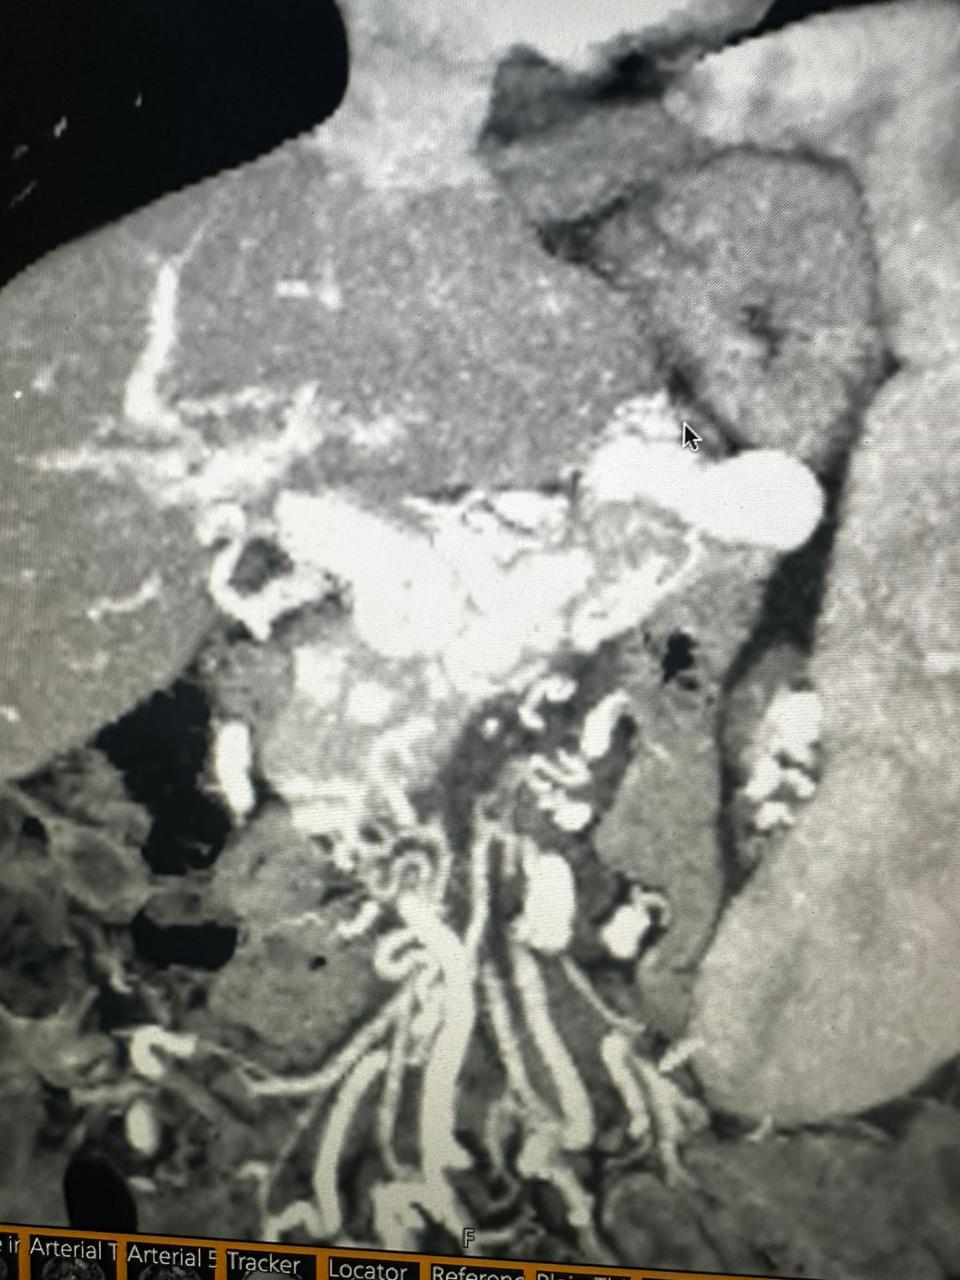

Peripheral Angioplasty procedure at Sarda Vascular Centre Dehradun

Interventional Radiology (IR) uses real-time imaging such as X-ray, ultrasound, CT, or MRI to guide tiny instruments through the body for treatment — without large surgical incisions.